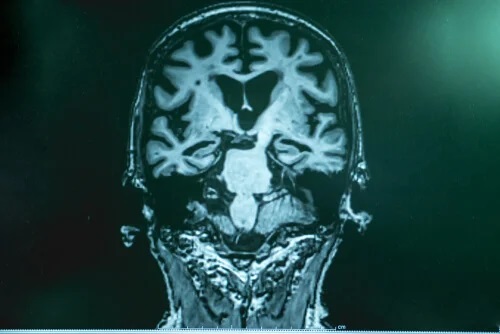

Dr. Lopera erklärt, dass bei Morbus Alzheimer eine Art Anhäufung von “Müll” im Gehirn stattfindet. Dieser “Müll” besteht aus sogenannten Amyloid-Proteinen. Sie sammeln sich an, verklumpen und bilden die unauflöslichen Ablagerungen zwischen den Nervenzellen, auch Alzheimer-Plaque genannt. Dadurch werden die Gehirnfunktionen gestört. Bei der Alzheimer-Erkrankung gibt es auch eine zweite Art von “Müll” – das chemisch veränderte Tau-Protein. Es sammelt sich in der Nervenzelle und lagert sich in Form von Fasern an die Neuronen an, was im Zellzerfall endet. Dieser Vorgang ist schädlicher für das Gehirn.